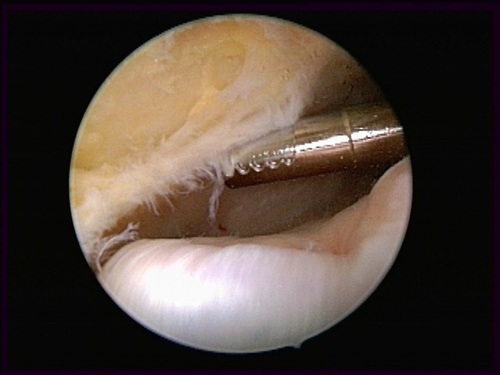

隱藏病灶                                                         手術清除中                                                      清除後